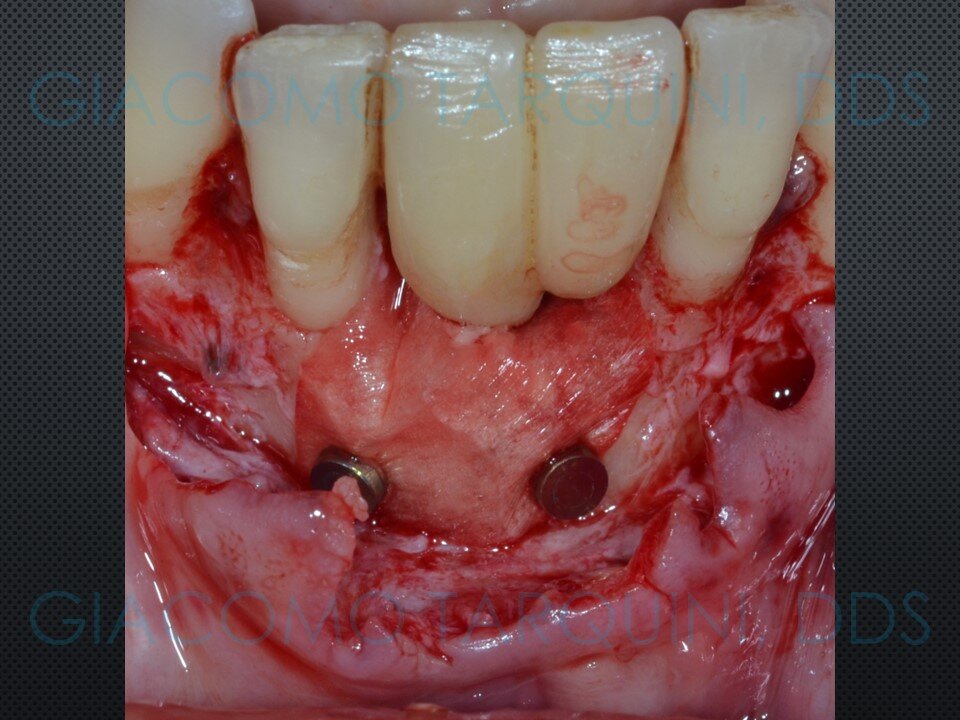

Viene presentato un caso di rigenerazione ossea guidata attorno a un impianto che aveva perso parte del suo supporto osseo a causa di una pregressa peri-implantite. Le spire esposte vengono decontaminate sfruttando le note proprietà della cavitazione ultrasonica per mezzo del dispositivo “Piezoclean by Dr. Giacomo Tarquini”, mentre la fase rigenerativa viene effettuata secondo il protocollo denominato “Poncho technique”. Questo approccio consente una ricostruzione prevedibile del tessuto osseo senza dover necessariamente rimuovere l'abutment e la protesi al fine di ottenere una guarigione sommersa.

CASO CLINICO: